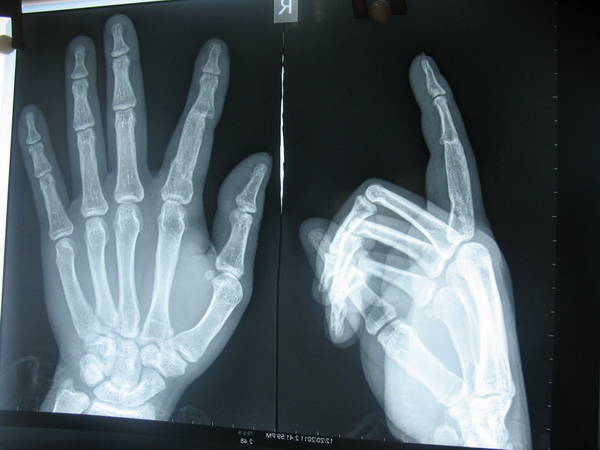

该病人于五月前外伤在本院行手术治疗,当时近指间关节及部分骨折缺如,当时因种种原因手术行了移植髂骨融合近指间关节,现病人手部功能活动受限,意愿行关节移植,请大家谈谈这个移植手术应该怎么做更好,我自己的想法,取对侧第二趾间关节移植,手部去除的髂骨修复第二足趾,移植手术病历少,不知术后功能恢复情况,听王增涛主任说关节移植后功能有恢复到手的80%左右,因患者当时手指复合组织缺损,现手屈指有力,伸指力量弱,手术中要行伸肌腱的重建,骨折的固定怎么样来选择,全髂骨是否要全部去除,大家共同来评论手术方法及愈后,谢谢